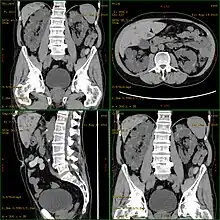

Diagnosis may be suspected from one, some, or all of the following: new onset flank pain or red urine; a positive family history; palpation of enlarged kidneys on physical exam; an incidental finding on abdominal sonogram; or an incidental finding of abnormal kidney function on routine lab work (BUN, serum creatinine, or eGFR). Definitive diagnosis is made by abdominal CT exam.

Polycystic kidney disease can be ascertained via a CT scan of abdomen, as well as, an MRI and ultrasound of the same area.[23] A physical exam/test can reveal enlarged liver, heart murmurs and elevated blood pressure.[1]